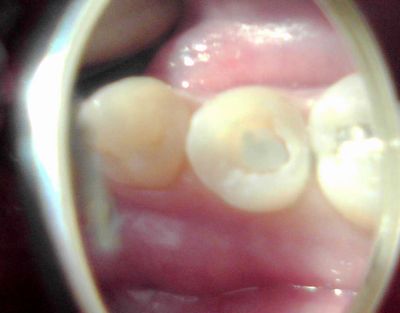

生活歯髄切断法ていうのは、例えばこんな齲蝕の深い症例で、

歯冠部の歯髄だけ除去して、根の部分の歯髄を残す治療法です。

以前はカルシペックスを使っていて、永久歯に対してはあまり予後が

良くなかったのですが、MTAセメントが出てからだいぶ変わりました。

で、MTA+GIセメントで覆髄、

CR充填。まあこれも、うまくいったと思っても何年か経ってから痛くなることもある。